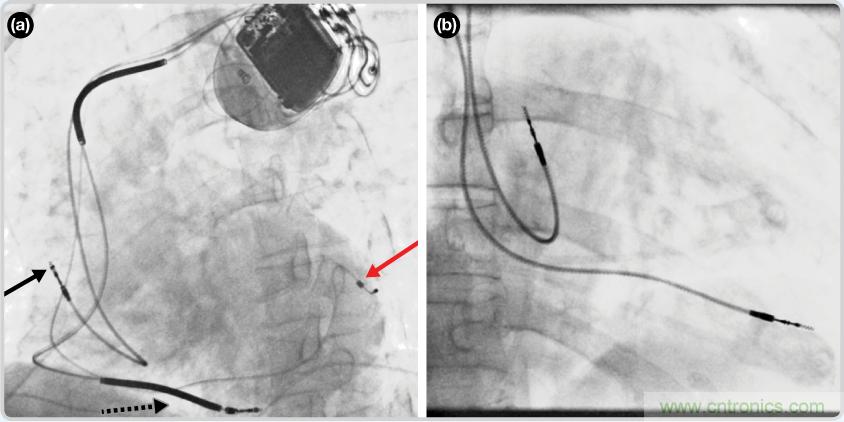

CRT器件在圖4(a)中的透視圖像中可以看見。醫(yī)師就是利用這種影像來(lái)放置導(dǎo)聯(lián)線的。對(duì)于非專業(yè)人士來(lái)說(shuō),這種影像是很難解讀的。可以看到心臟淡淡的輪廓——這是搏動(dòng)中的心臟的靜態(tài)視圖。起搏器位于右心房上,心臟頂點(diǎn)指向右下方。在這個(gè)典型的導(dǎo)聯(lián)線放置實(shí)例中,黑色箭頭指向右心房導(dǎo)聯(lián)線。虛線黑色箭頭指向右心室導(dǎo)聯(lián)線。紅色箭頭標(biāo)示的導(dǎo)聯(lián)線只能看到一部分,這是左心室導(dǎo)聯(lián)線(紅箭頭指向電極尖端)。圖4(b)展示的是雙腔起搏器的典型導(dǎo)聯(lián)線放置透視圖像。右心房導(dǎo)聯(lián)線指向上方,置于右心房中。右心室導(dǎo)聯(lián)線則位于右心室頂部。

檢測(cè)并區(qū)分心臟起搏偽像

圖4. 起搏器導(dǎo)聯(lián)線放置的透視圖像3 (a). 單腔起搏器;(b).雙腔起搏器